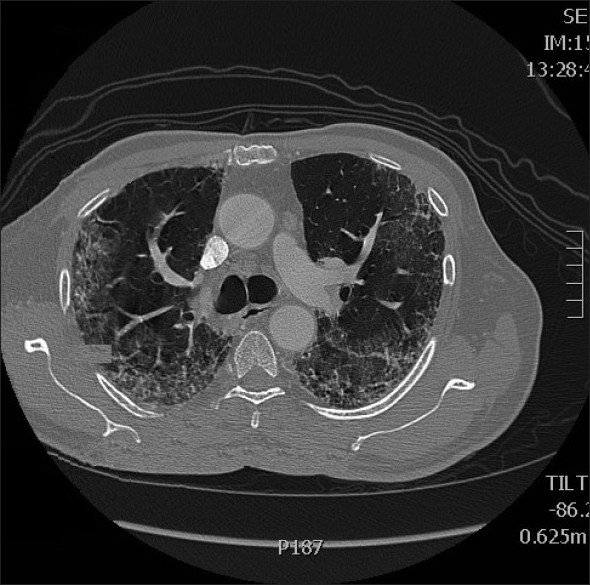

Adjuvant chemotherapy with oxaliplatin given at a dose of 130 mg/m2 intravenously on Day 1 of each three-week cycle, and capecitabine at a dose of 2000 mg/m2/day orally in two divided doses was given on Days 1–14 of each cycle.[4] The patient tolerated the initial cycle well; however, after the second cycle of the treatment, which was three weeks later, he developed progressive dyspnea and persistent cough despite having no history of any previous lung disease, and a pre-treatment chest X-ray was normal. A chest radiograph revealed diffuse bilateral interstitial infiltrates and an ABG performed showed significant hypoxia with PaO2 of 55 mmHg. A high resolution computed tomography (HRCT) scan [Figures [Figures11 and and2]2] showed bilateral alveolar infiltrates predominant in the bases. A trans-bronchial lung biopsy could not be performed as he was extremely breathless and hypoxic. He was commenced on 80 mg of methylprednisolone thrice a day. However his clinical condition began to deteriorate and within a week of starting steroids he succumbed to his illness.

| Figure 1 High resolution computed tomography scan 1